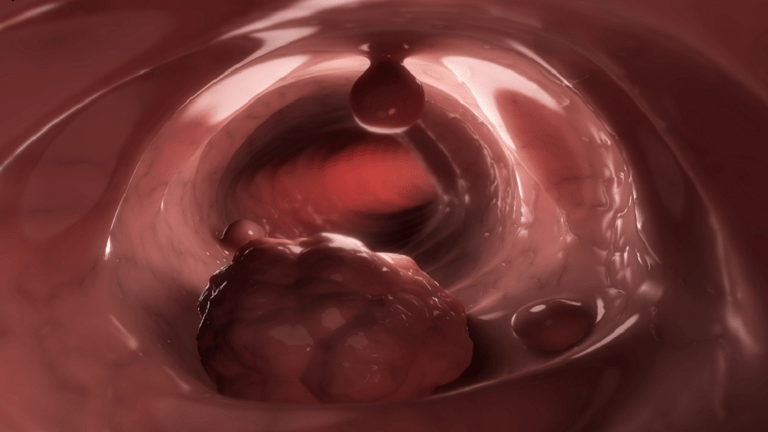

مشروب شائع ثبت أنه يزيد من خطر الإصابة بسرطان الأمعاء بـ”دليل قوي”!

وفقا لـ AICR، هناك “دليل قوي” على أن استهلاك الكحول يزيد من خطر الإصابة بسرطان الأمعاء. ويزيد تناول ثلاثة مشروبات كحولية أو أكثر يوميا (45 غراما أو أكثر) من المخاطر. والآليات الدقيقة الكامنة وراء العلاقة بين استهلاك الكحول وأنواع معينة من السرطان ليست مفهومة تماما.